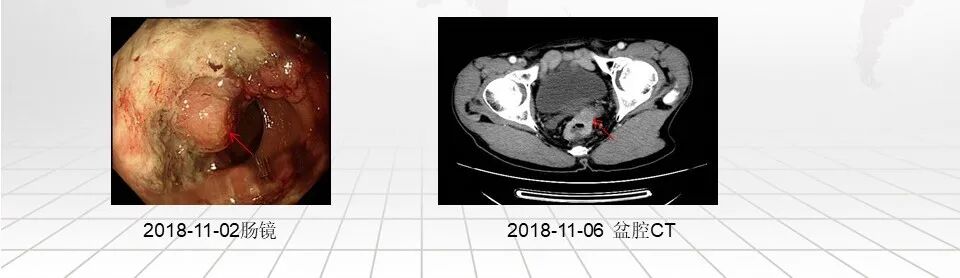

2018年11月因“大便形状改变2月”就诊于肥西县人民医院,电子肠镜检查提示:距肛门5 cm处见一隆起性新生物,表面充血糜烂,顶端凹陷,活检弹性差,质脆易出血。直肠癌可能。

电子肠镜(肥西县人民医院):距肛门5 cm处见一隆起性新生物,表面充血糜烂,顶端凹陷,活检弹性差,质脆易出血。直肠Ca可能。

胸腹盆腔平扫+增强CT(我院):考虑直肠癌,左侧精囊腺受侵可能,伴周围淋巴结肿大。双肺纤维灶。右肾内小囊肿。前列腺钙化灶。